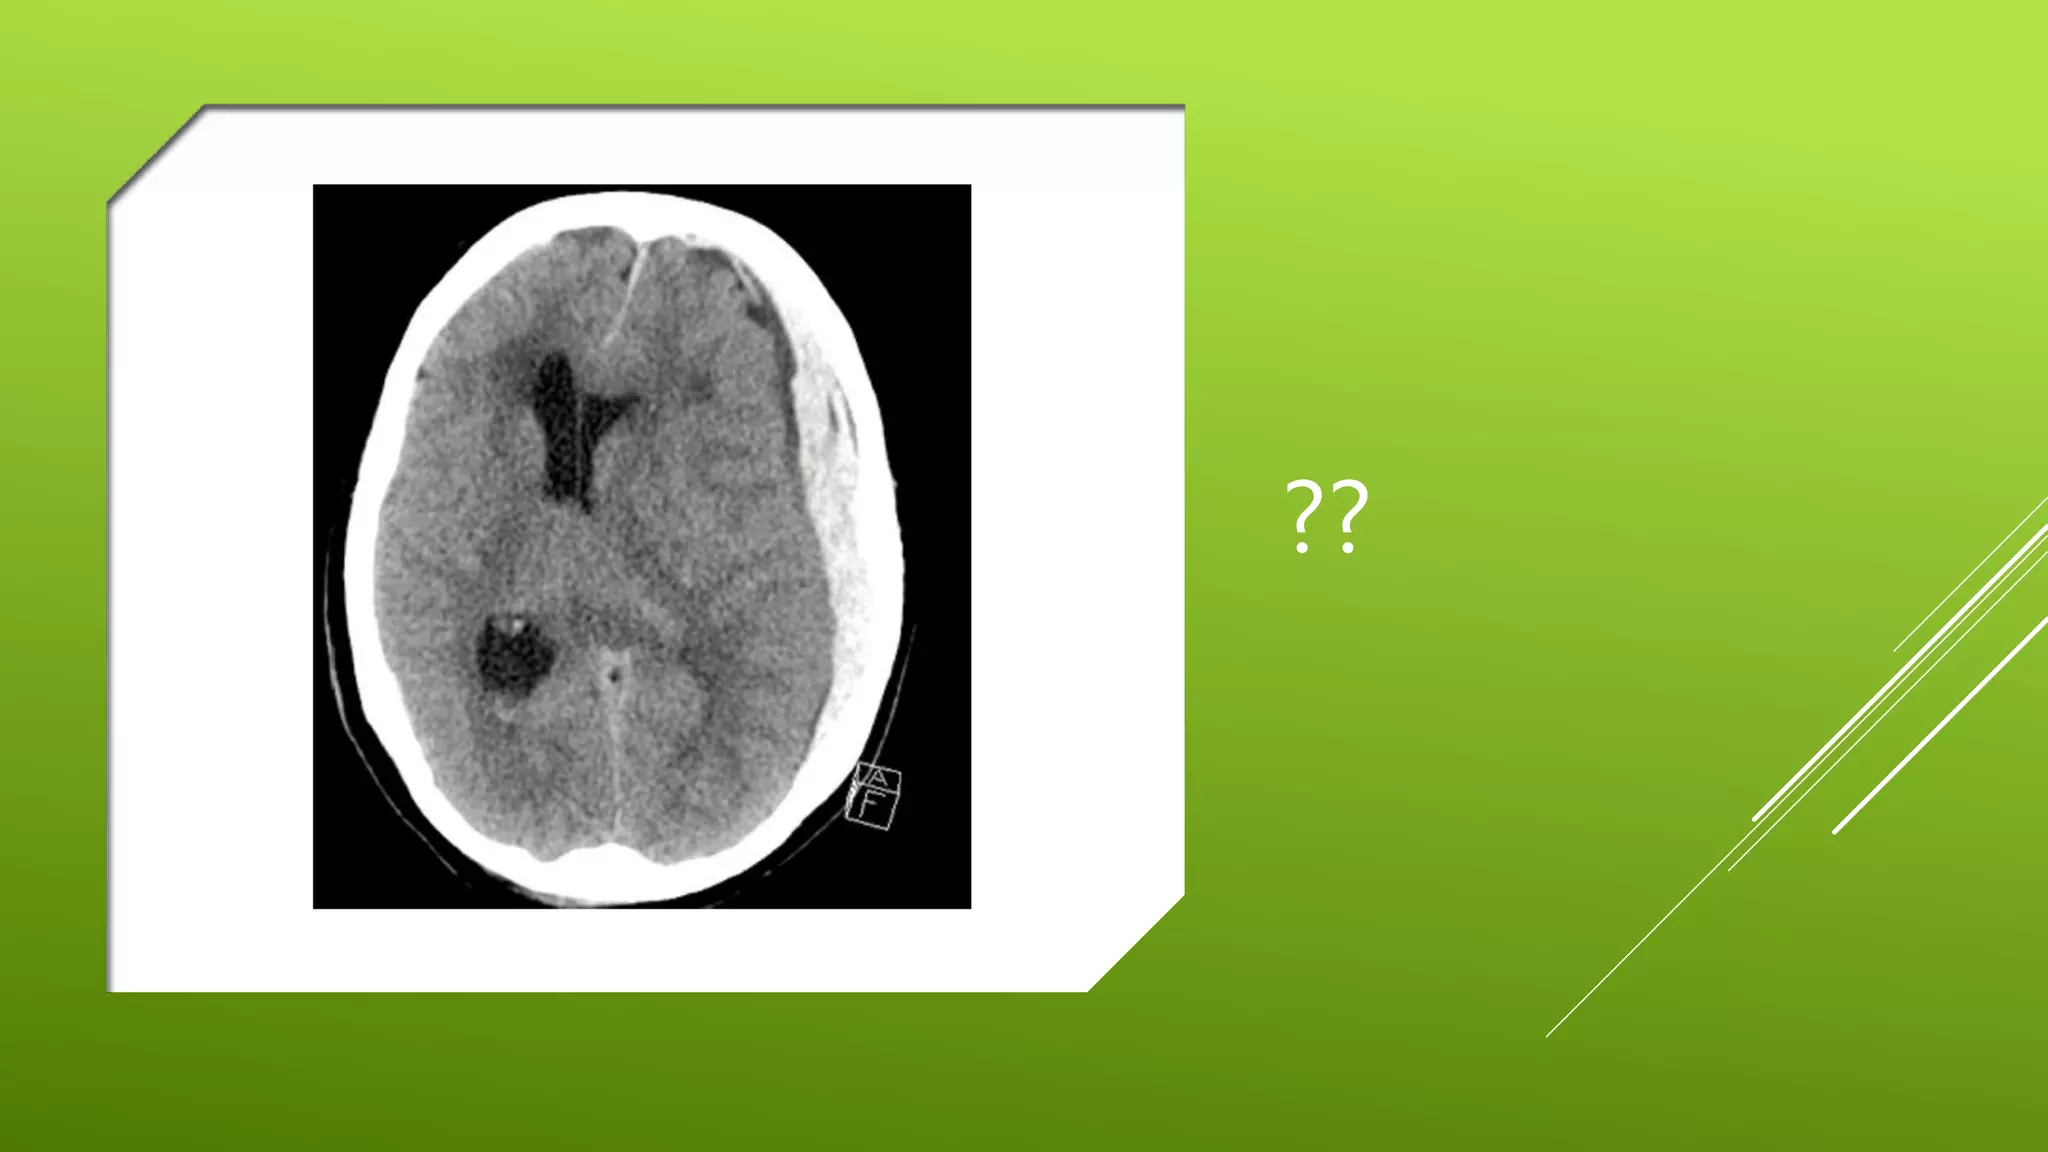

This document contains a series of radiology-related questions and prompts seeking identification and interpretation of various imaging findings, patient presentation details, monitoring values, scoring systems, diagnoses, and management steps. Specific topics include identifying x-ray and CT scan findings, interpreting EKG results, recognizing arrhythmias, assessing intubated and post-surgery patients, and evaluating compliance with treatment plans.